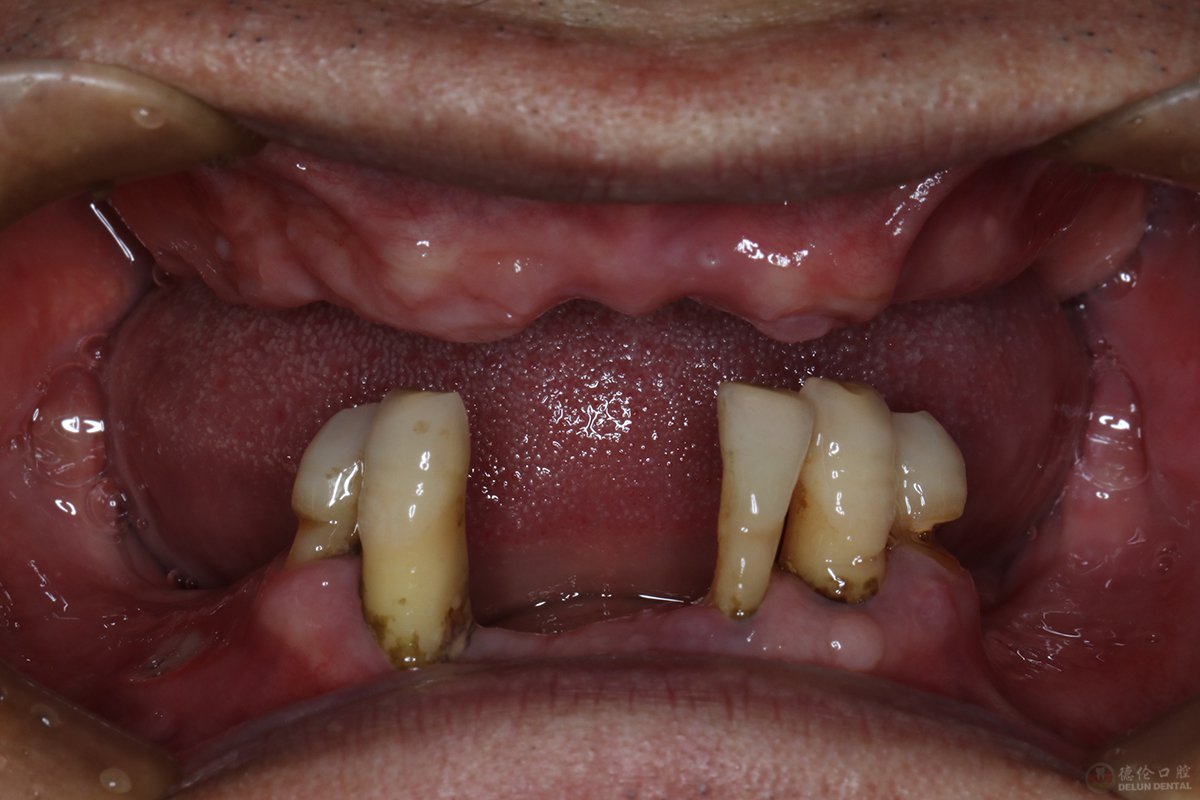

牙齿症状:上颌牙全部缺失、下颌牙缺失多颗(仅剩4颗)

主要诉求:寻找到一种省时、耐用的修复方法;解决无牙吃饭、咀嚼的烦恼

治疗方式:上颌ALL-ON-6种植牙+下颌活动义齿

治疗前后:

直到2017年,苏先生的牙齿已经到了上半口牙全部缺失、下半口牙仅剩4、5颗的地步,多年来,活动假牙不适的问题依然困扰着他,然而却找不到好的方法。没想到当年轻易拔牙之举、平时口腔意识薄弱、多年戴活动假牙等这些行为竟然会导致牙齿沦为这般模样。

根据苏先生的口腔状况以及个人的其他情况,万医生及其医护团队为其定制了上颌ALL-ON-6种植牙+下颌活动义齿的修复方案。万医生表示:像苏先生一样,很多人的牙齿只是缺失1、2颗,不影响生活,如果不及时修复治疗,缺牙很可能会更加严重,修复的代价更大。